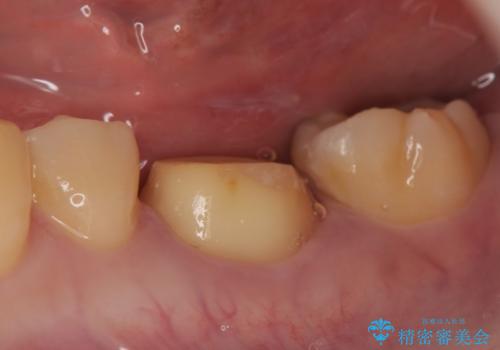

- 左下6の歯が欠けてしまったので診て欲しいといらっしゃった方の症例です。

虫歯除去後、オールセラミッククラウンによる補綴を行いました。